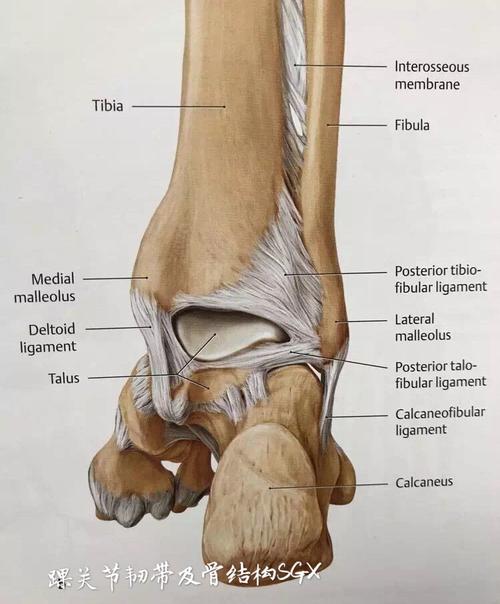

高清图解踝关节韧带解剖

踝关节解剖分析

值得收藏踝关节解剖分析高清图文详解

踝关节损伤的病因如何处理以及预防措施(附踝关节解剖

踝关节损伤的病因如何处理以及预防措施(附踝关节解剖